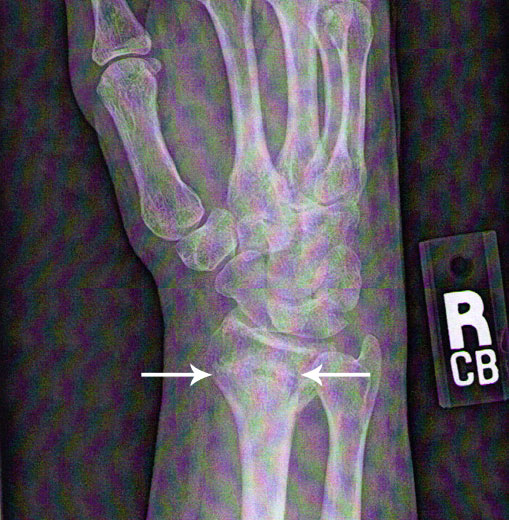

The images below show a wrist break and then after the use of photon light therapy and bone density repairing supplements. This occurred in less than one month.

After Treatment at IWBW